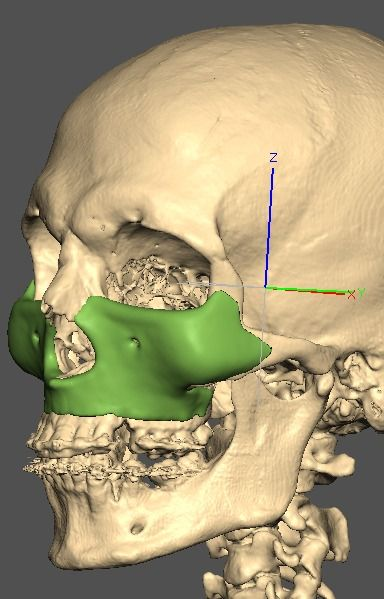

I know a guy who designed this for himself in collaboration with an asian implant company.

Not the final product yet, he is making adjustments as we speak.

Found a surgeon willing to insert it.

Giant and Eppley were the inspiration